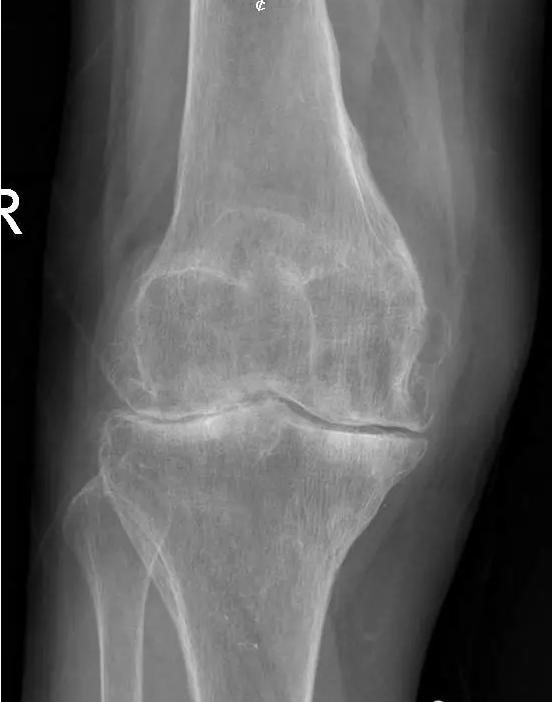

中期:骨关节炎表现为膝关节持续性疼痛,活动后或上下楼梯时加重,压痛明显; X线片上可见增生的骨赘,关节间隙出现狭窄,多为不对称性狭窄。

晚期:骨关节炎表现为膝关节明显疼痛,休息后常无缓解,伴有活动受限,可并发畸形,X 线片可见关节周围有明显的骨赘形成,或可见游离体,关节间隙明显狭窄,甚至消失。

术前片: